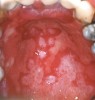

Figure 5  Oral presentation of GVHD.

Figure 5